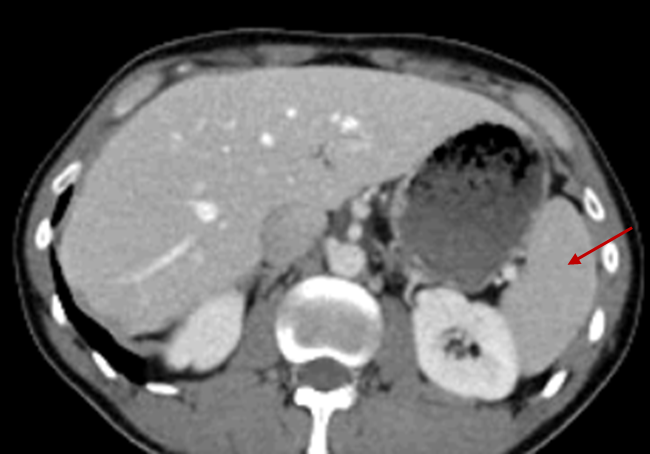

2.148 Der rote Pfeil markiert im folgenden CT-Thorax ein Organ. Welche Aussage zu diesem Organ stimmt zu?

- (A) In seinem Inneren findet die Bildung von Albumin und Gerinnungsfaktoren statt.

- (B) Seine venöse Drainage erfolgt primär über die Vena renalis direkt in die Vena cava inferior.

- (C) Es ist ein lymphatisches Organ, in dessen roter Pulpa die Aussonderung alter Erythrozyten erfolgt

- (D) Es besitzt eine Curvatura major, an der das Omentum majus befestigt ist.

- (E) Es verfügt über endokrine Zellansammlungen, die für die Regulation des Blutdrucks relevant sind